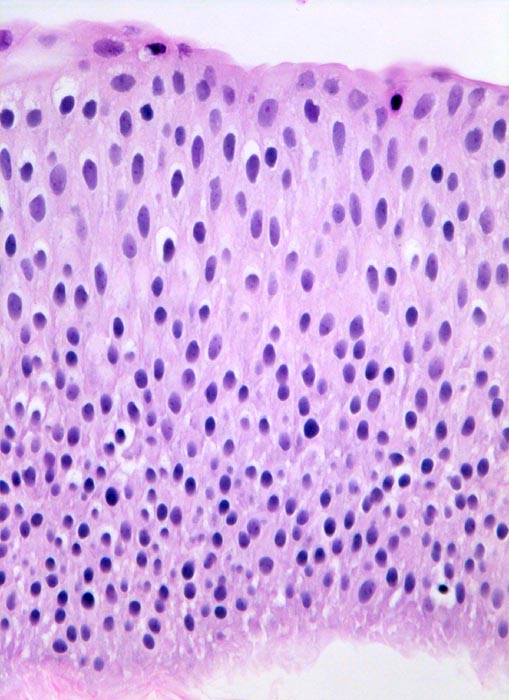

PathoPic ID 5045 - Nicht invasives papilläres Urothelkarzinom pTa

Nicht invasives papilläres Urothelkarzinom pTa

Das bedeckende Urothel des papillären Tumors ist deutlich verbreitert. Zellatypien sind nicht vorhanden (histologischer Grad 1).

Normales Urothel umfasst in der Regel weniger als 7 Zellagen.